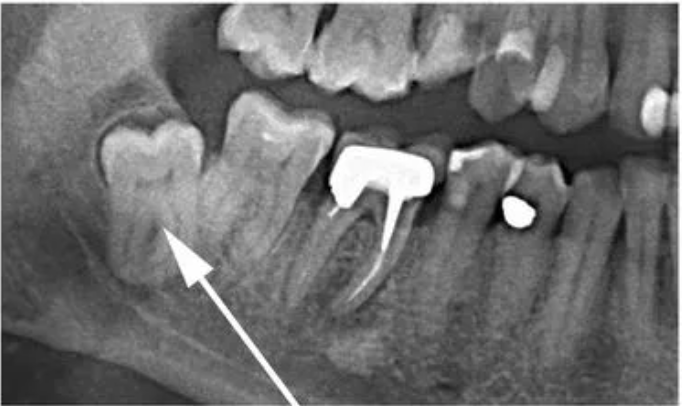

1. Атипичное положение: если зуб мудрости растет под углом или направлен в сторону других зубов, это может привести к повреждению корней и развитию инфекций. В запущенных случаях придется удалять не только зуб мудрости, но и соседние зубы.

атипичное положение зуба мудрости